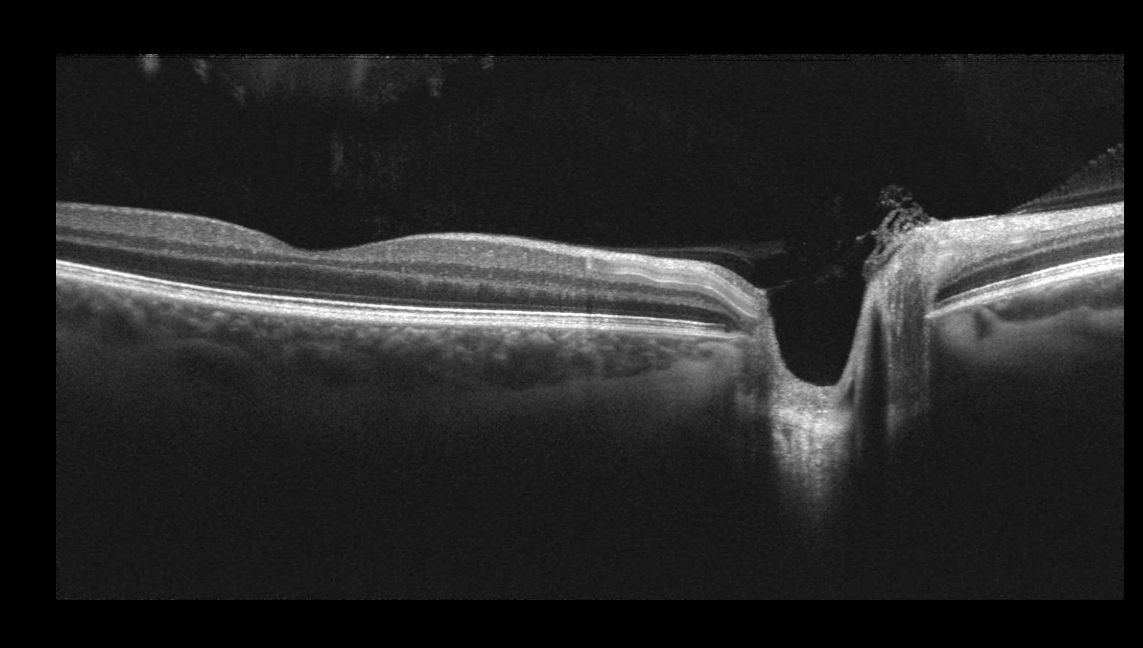

OCT provides detailed cross-sectional images of the retina and optic nerve, allowing us to assess the eye’s deeper structures with precision.

It plays an important role in identifying and monitoring conditions such as glaucoma and macular disease, often before noticeable symptoms develop.

Used thoughtfully and when clinically appropriate, OCT helps guide informed decisions and long-term eye health planning.